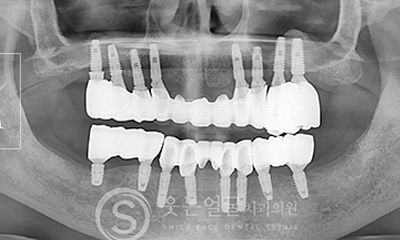

8천여건의 다양한

임플란트 수술 케이스

다년간 축적된 8,000여 건 이상의

임플란트 수술 경험을 바탕으로,

환자 개개인의 구강 구조와

상태에 최적화된 안전하고 정확한 시술을 제공합니다.